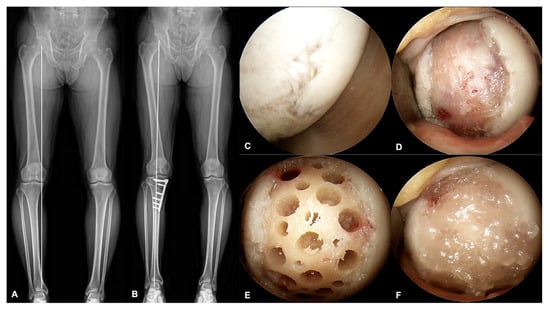

| HKA angle | 173.3 ± 2.8 |

| Degree of defect repair | 3.5 ± 0.5 | |

| Integration to the border zone | 2.5 ± 1.1 | |

| Macroscopic appearance | 2.4 ± 1.0 | |

| Total score (mean ± SD) | 0–12 | 8.4 ± 2.3 |

| Grading system * | n (%) | |

| Grade 1: Normal | 12 | 1 (10) |

| Grade 2: Nearly normal | 8–11 | 7 (70) |

| Grade 3: Abnormal | 5–7 | 2 (20) |

| Grade 4: Severely abnormal | 0–4 | 0 (0) |